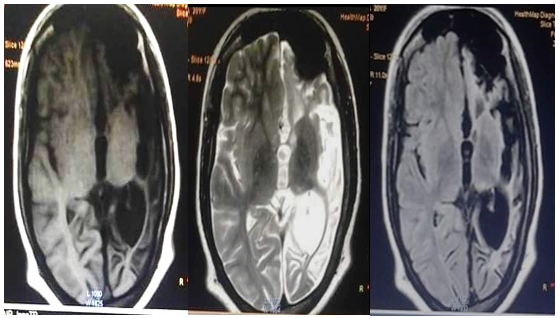

She underwent various cross-sectional imaging. Axial Non-contrast Computed tomography (NCCT) of brain depicts left cerebral hemisphere atrophy with dilatation of ipsilateral lateral ventricle with a bone window showing thickening of the left hemicranium, almost twice the thickness of that on the right side in the temporal region and hyperpneumatization of the left frontal sinuses [Figure 1].

In addition to that, Magnetic Resonance Imaging (MRI) brain demonstrates diffuse cortical and subcortical atrophy as hyperintensities on T2, T2 FLAIR (Fluid Attenuation Inversion Recovery) and hypointensities in T1 sequences, however the left basal ganglia was relatively spared [Figure 2].